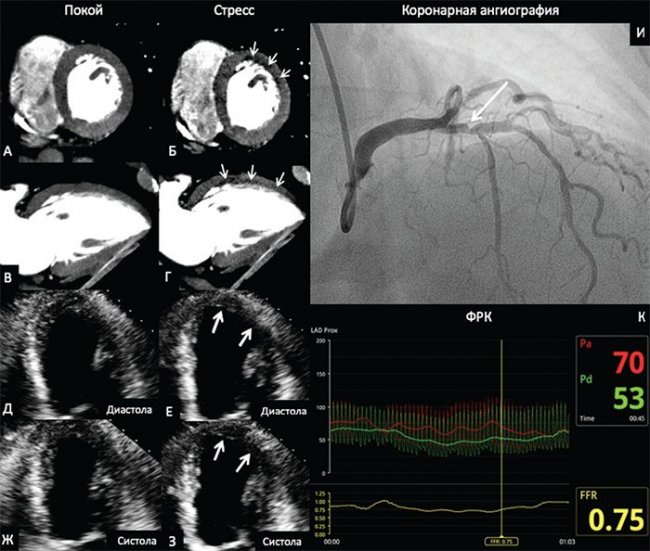

В качестве примера на рис. 2 приведены данные ПКТ с ЧПЭС, стресс-ЭхоКГ с ВЭМ и КАГ с ФРК больного 69 лет с ОКС. По данным ПКТ был выявлен преходящий дефект перфузии, а при проведении стресс-ЭхоКГ – гипокинез средних сегментов, верхушечных передней и переднебоковой локализации. При КАГ выявлен стеноз 70% проксимального сегмента передней нисходящей артерии, значение ФРК составило 0,75.

Рисунок 2. Перфузионная компьютерная томография миокарда, стресс-эхокардиография и коронарная ангиография с измерением фракционного резерва кровотока

На изображениях ПКТ в покое (рис. 2А, 2В) определяется равномерное контрастирование миокарда ЛЖ. На эхокардиограмме в апикальной четырехкамерной позиции (рис. 2Д, 2Ж) отсутствуют зоны нарушения локальной сократимости ЛЖ в покое. На фоне проведения стресс-теста на изображениях ПКТ (рис. 2Б, 2Г) определяется зона пониженного контрастирования (зона дефекта перфузии – стрелки) переднебоковой локализации ЛЖ. На эхокардиограммах в фазе стресса (рис. 2Е, 2З) определяется зона гипокинеза переднебоковой локализации ЛЖ (рис. 2, стрелки). На коронарограмме (рис. 2И) визуализируется 70%-й стеноз проксимального сегмента передней нисходящей артерии (рис. 2И, стрелка). ФРК составил 0,75, что свидетельствует о гемодинамической значимости стеноза.